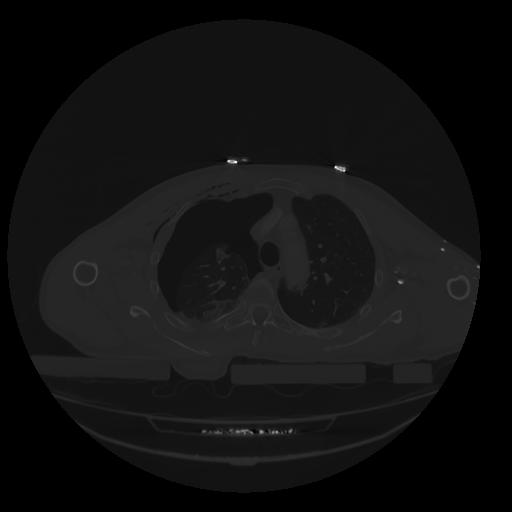

28 CUERPO,CE,Vol,2.0,CUERPO,,